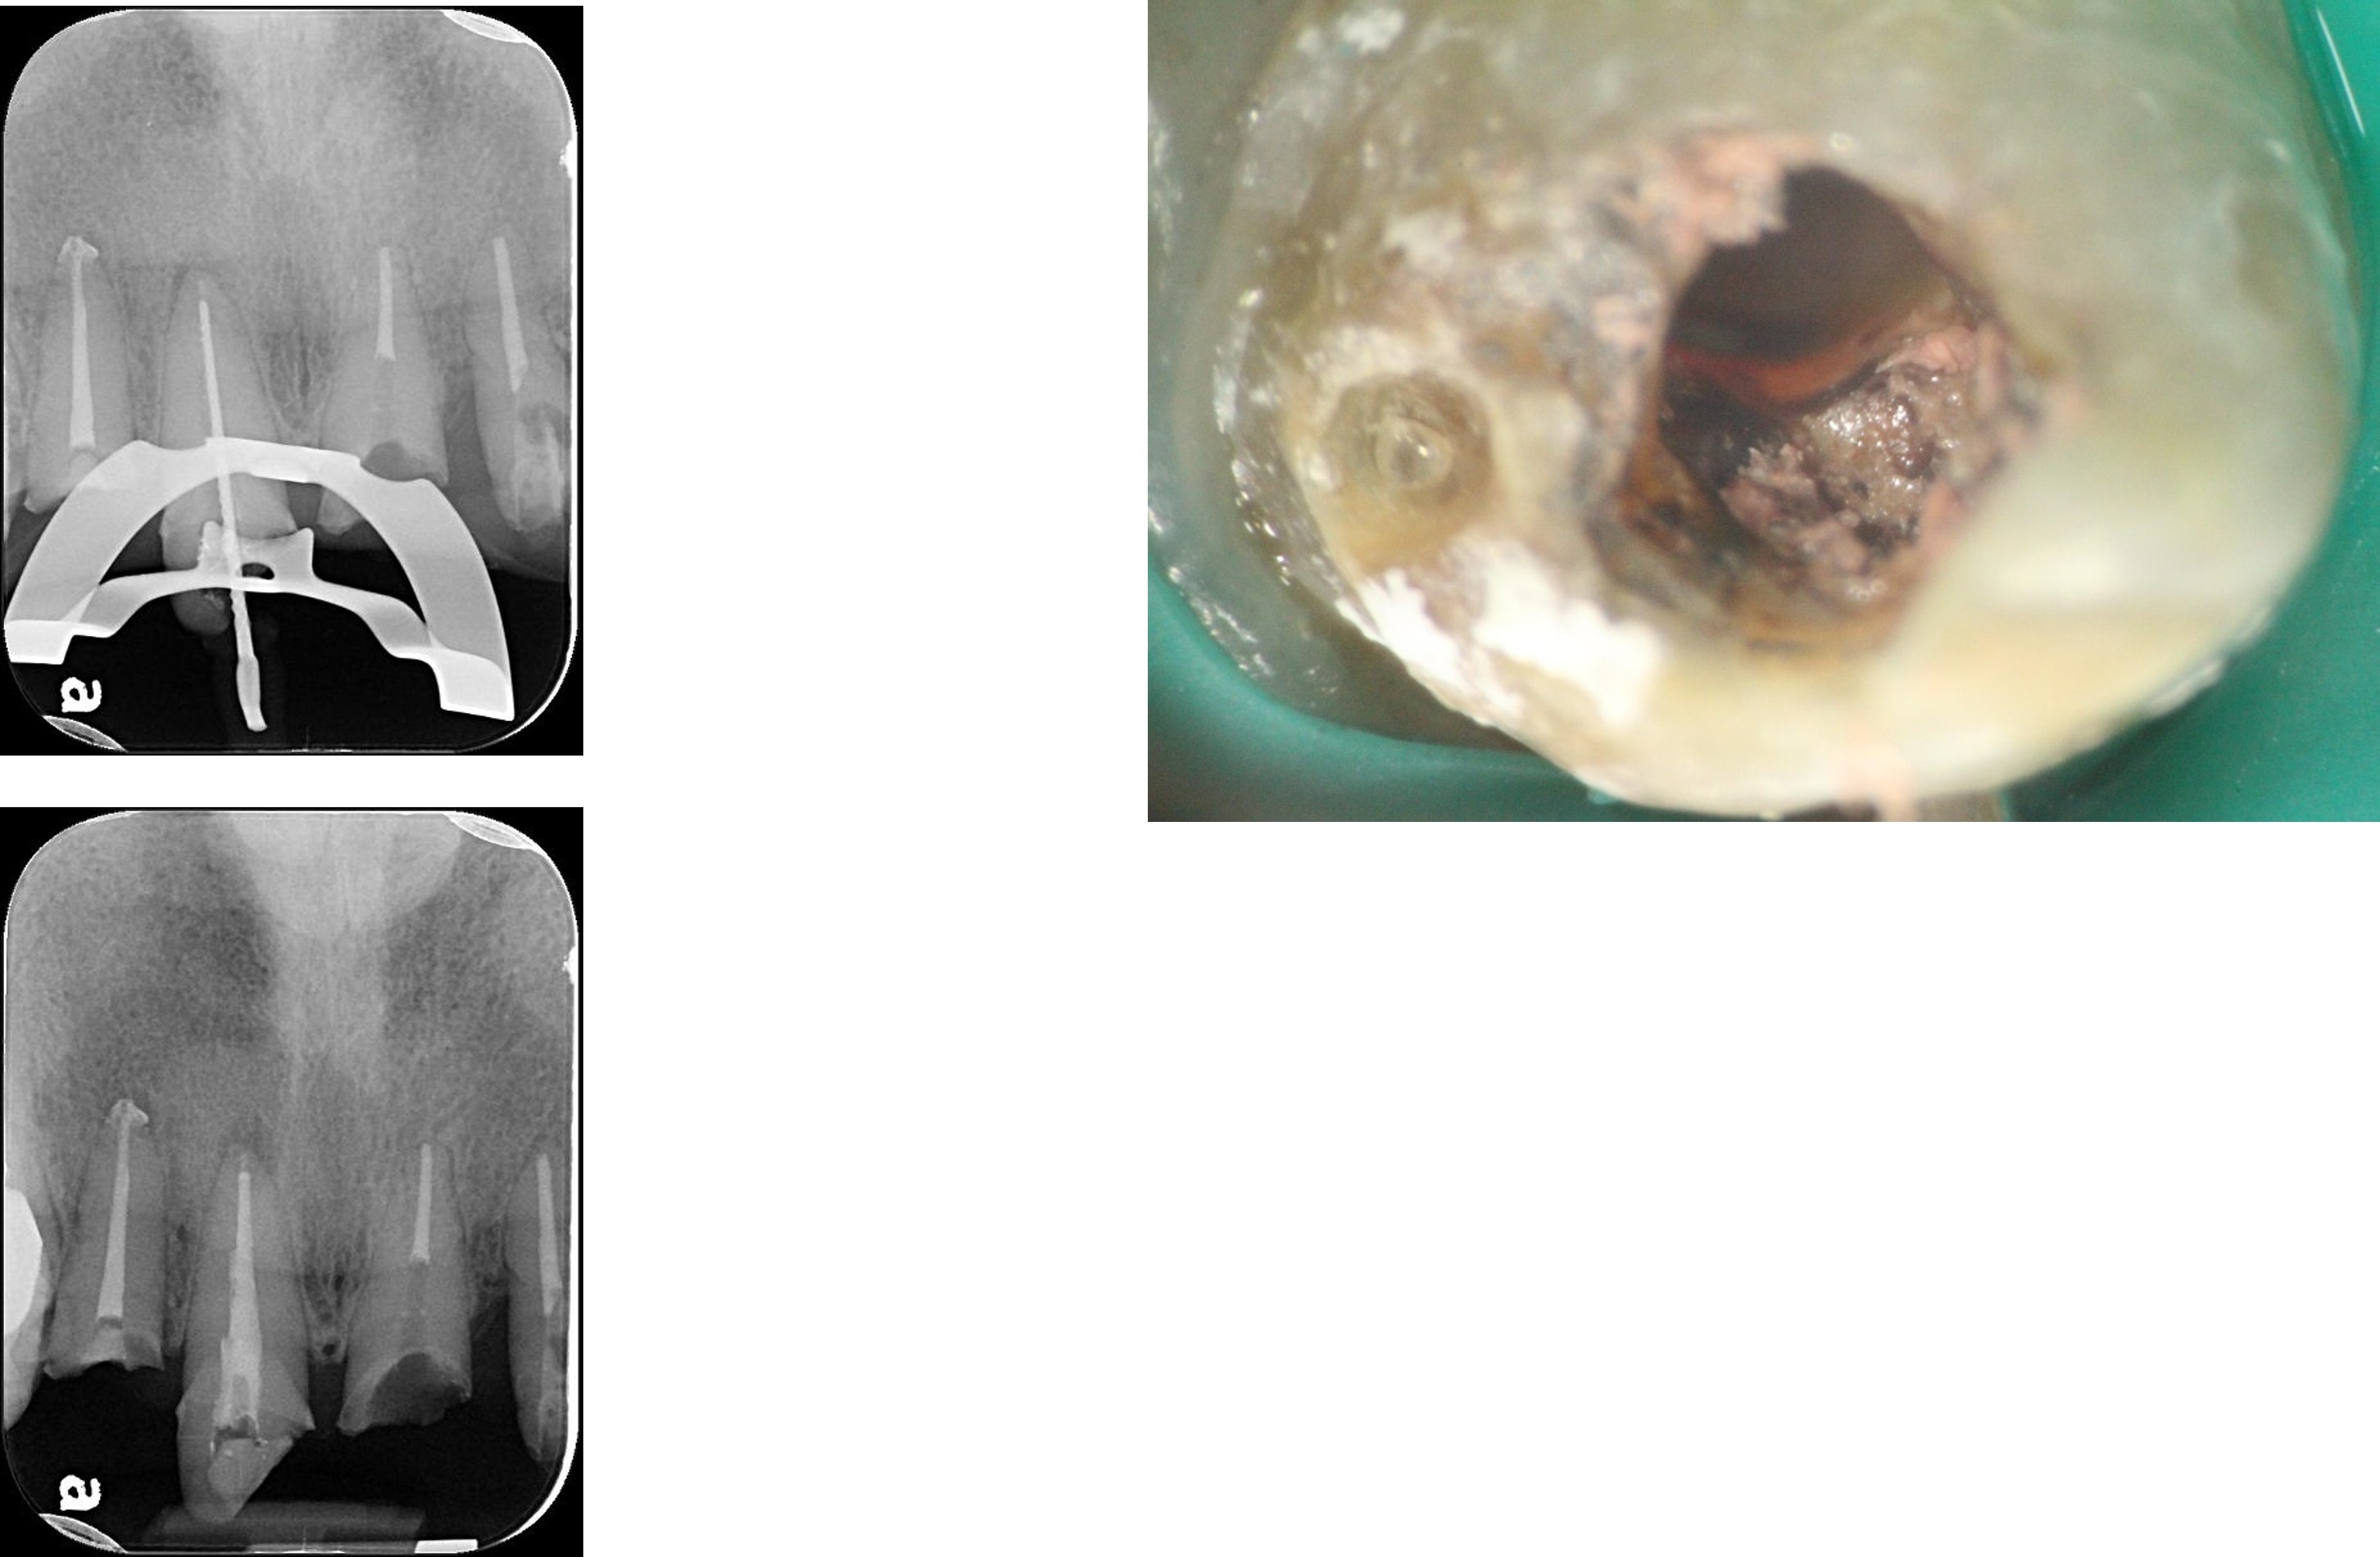

1)電腦定位手術模板

照相比色

面弓轉移,上咬合器

咬合器上製作瓷牙

前牙及植牙全瓷冠